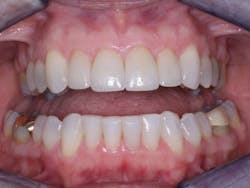

Making the decision whether to place an intracoronal restoration, an inlay, an onlay, or a crown is not a difficult one. The decision is made by considering the patient’s overall systemic and oral health characteristics, esthetic desires, and specific tooth characteristics. Currently available crowns are superb when done properly (figure 6); just don’t do them before they are indicated.